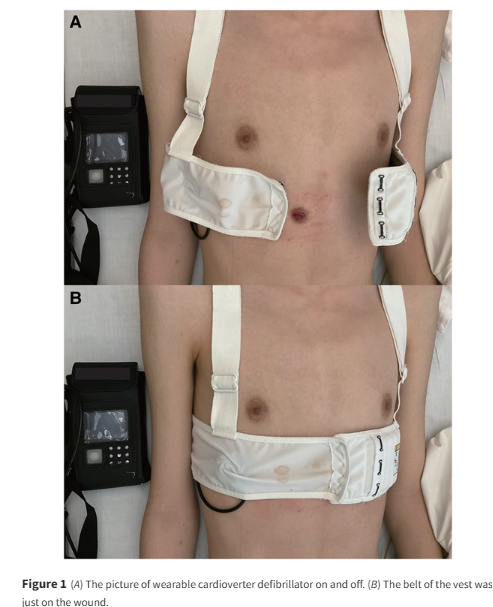

An unusual complication from a wearable cardioverter defibrillator ow.ly/vEnZ50VSngM #EHJCaseReports Philipp Sommer Tee Joo YEO Aaysha Cader Boldizsar Kovacs Erik Rafflenbeul A.Nazmi Calik Obayda Azizy Sara Moscatelli EHJCaseReports Editor-in-Chief #CardioX #EPeeps